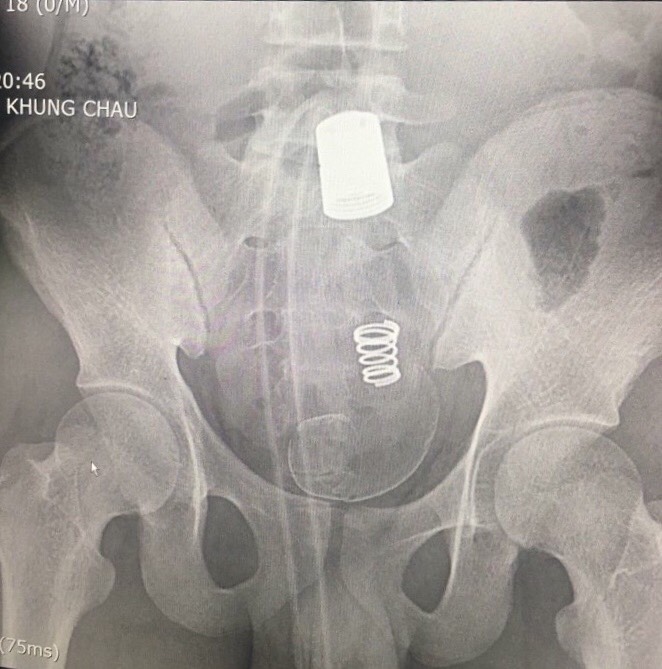

Bệnh viện đa  khoa tỉnh Hải Dương vừa phẫu thuật thành công cho một trường hợp có dị vật lớn đại trực tràng

03/08/2018 (GMT+7)

Ngày 22 tháng 07 các Bác sĩ Bệnh viện đa khoa tỉnh Hải Dương vừa phẫu thuật thành công cho một trường hợp bệnh nhân 18 tuổi, có dị vật lớn đại tràng sigma và trực tràng do tự hại. Đây là trường hợp bệnh hiếm gặp trong nhiều năm tại Bệnh viện và cũng có bệnh cảnh rất đặc biệt.